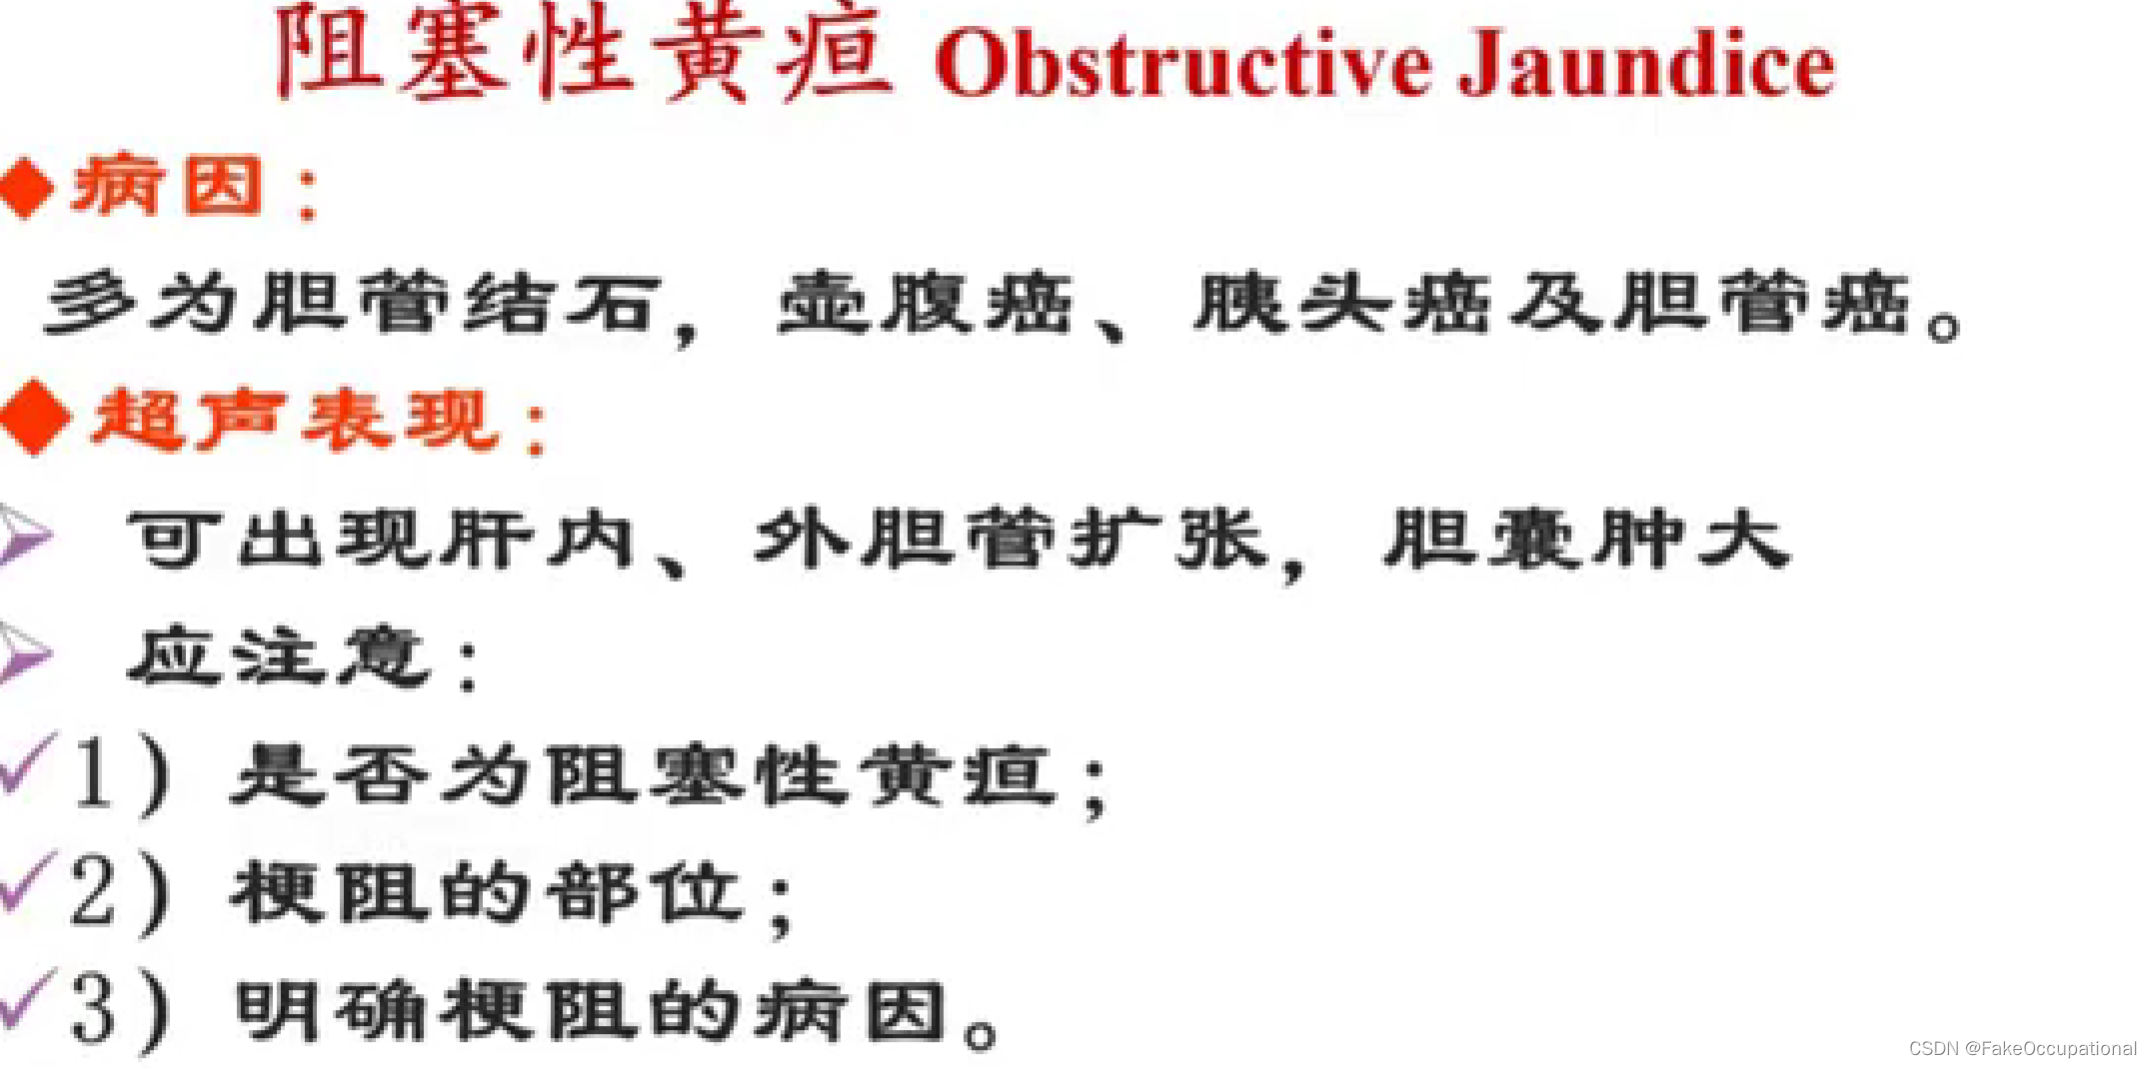

- (五)阻塞性黄疸的鉴别诊断

黄疽:血清内胆红素浓度增高。引起巩膜、皮肤、粘膜、体液、其他组织的黄染

临床分型:肝前性黄疸(溶血性黄痘、非溶血性)、肝性黄痘及肝后性黄疸(阻寒性黄疸)